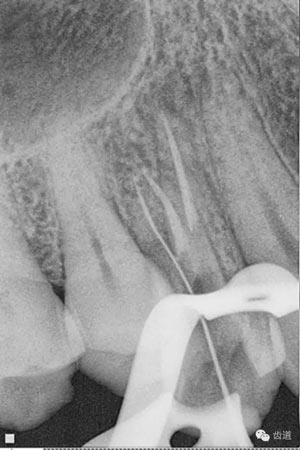

數(shù)碼攝影x片顯示:14遠(yuǎn)中鄰頜面暗影,穿髓。根尖暗影。無(wú)牙周膜增寬。

處理:去除暫封物,超聲根管蕩洗,清除氫氧化鈣糊劑,干燥根管,拍片顯示2506牙膠尖適合,根管內(nèi)放置AH plus,熱牙膠連續(xù)波根管充填。

數(shù)碼x攝影顯示:近中頰根及腭根根管充填恰填,遠(yuǎn)中根管有遺漏。